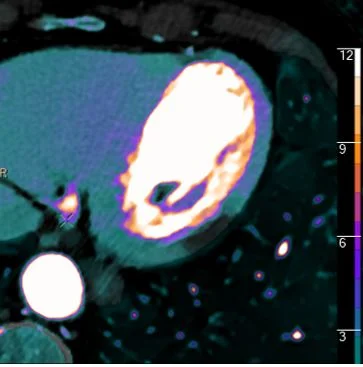

Something new for adrenal nodules